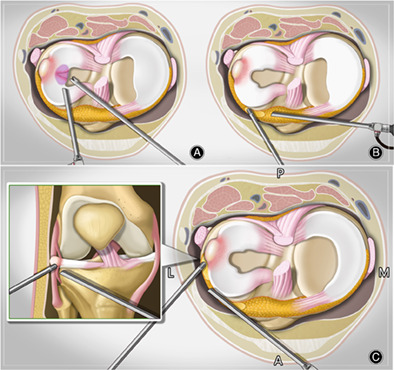

Compared with the traditional arthroscopic cyst excision, the modified arthroscopic cyst excision can preserve the stable structures of the meniscus synovial rim and can clearly show the inner and surrounding tissues of the parameniscal cyst. The modified procedure is shown in Figure 2. Arthroscopic photographs show the whole process in Figure 3.

FIG. 2.

The operation procedure by a modified fat pad approach. (A) An anterolateral portal was established to perform the arthroscopic diagnosis. The anteromedial portal was established to probe, debride and reshape the torn meniscus. (B) A passageway to the cyst was made by shaver through the anterolateral fat pad at the level of the lateral meniscus with the stable structure of the femoral and tibial sides of the meniscus intact. (C) An extra lateral portal beside the cysts was made under arthroscopic view. The arthroscopy and shaver were inserted in the anteromedial and anterolateral portals, respectively, to expose the cysts laterally and remove them horizontally along with the meniscus from the planned level of the fat pad.